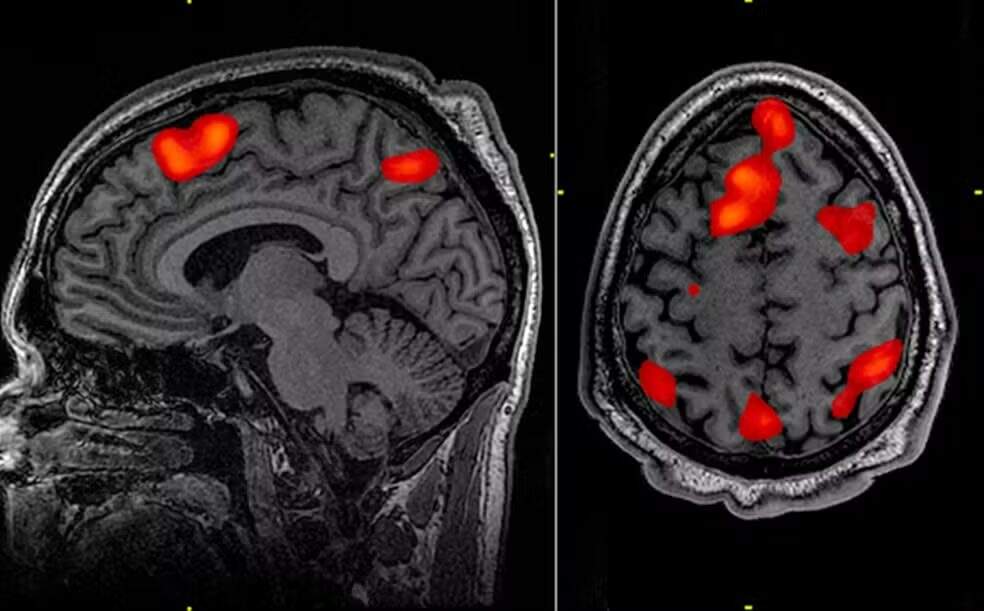

Ele é introduzido profundamente no cérebro, usando imagens de ressonância magnética para orientar um microcateter em duas regiões do cérebro, o núcleo caudado e o putâmen. A neurocirurgia leva entre 12 e 18 horas.

Os dados demonstram que, três anos após a cirurgia, houve, em média, 75% de redução da velocidade de avanço da doença, com base em uma medição que combina a cognição, funções motoras e a capacidade de se autogerenciar no dia a dia. Os dados também demonstram que o tratamento está salvando as células cerebrais.